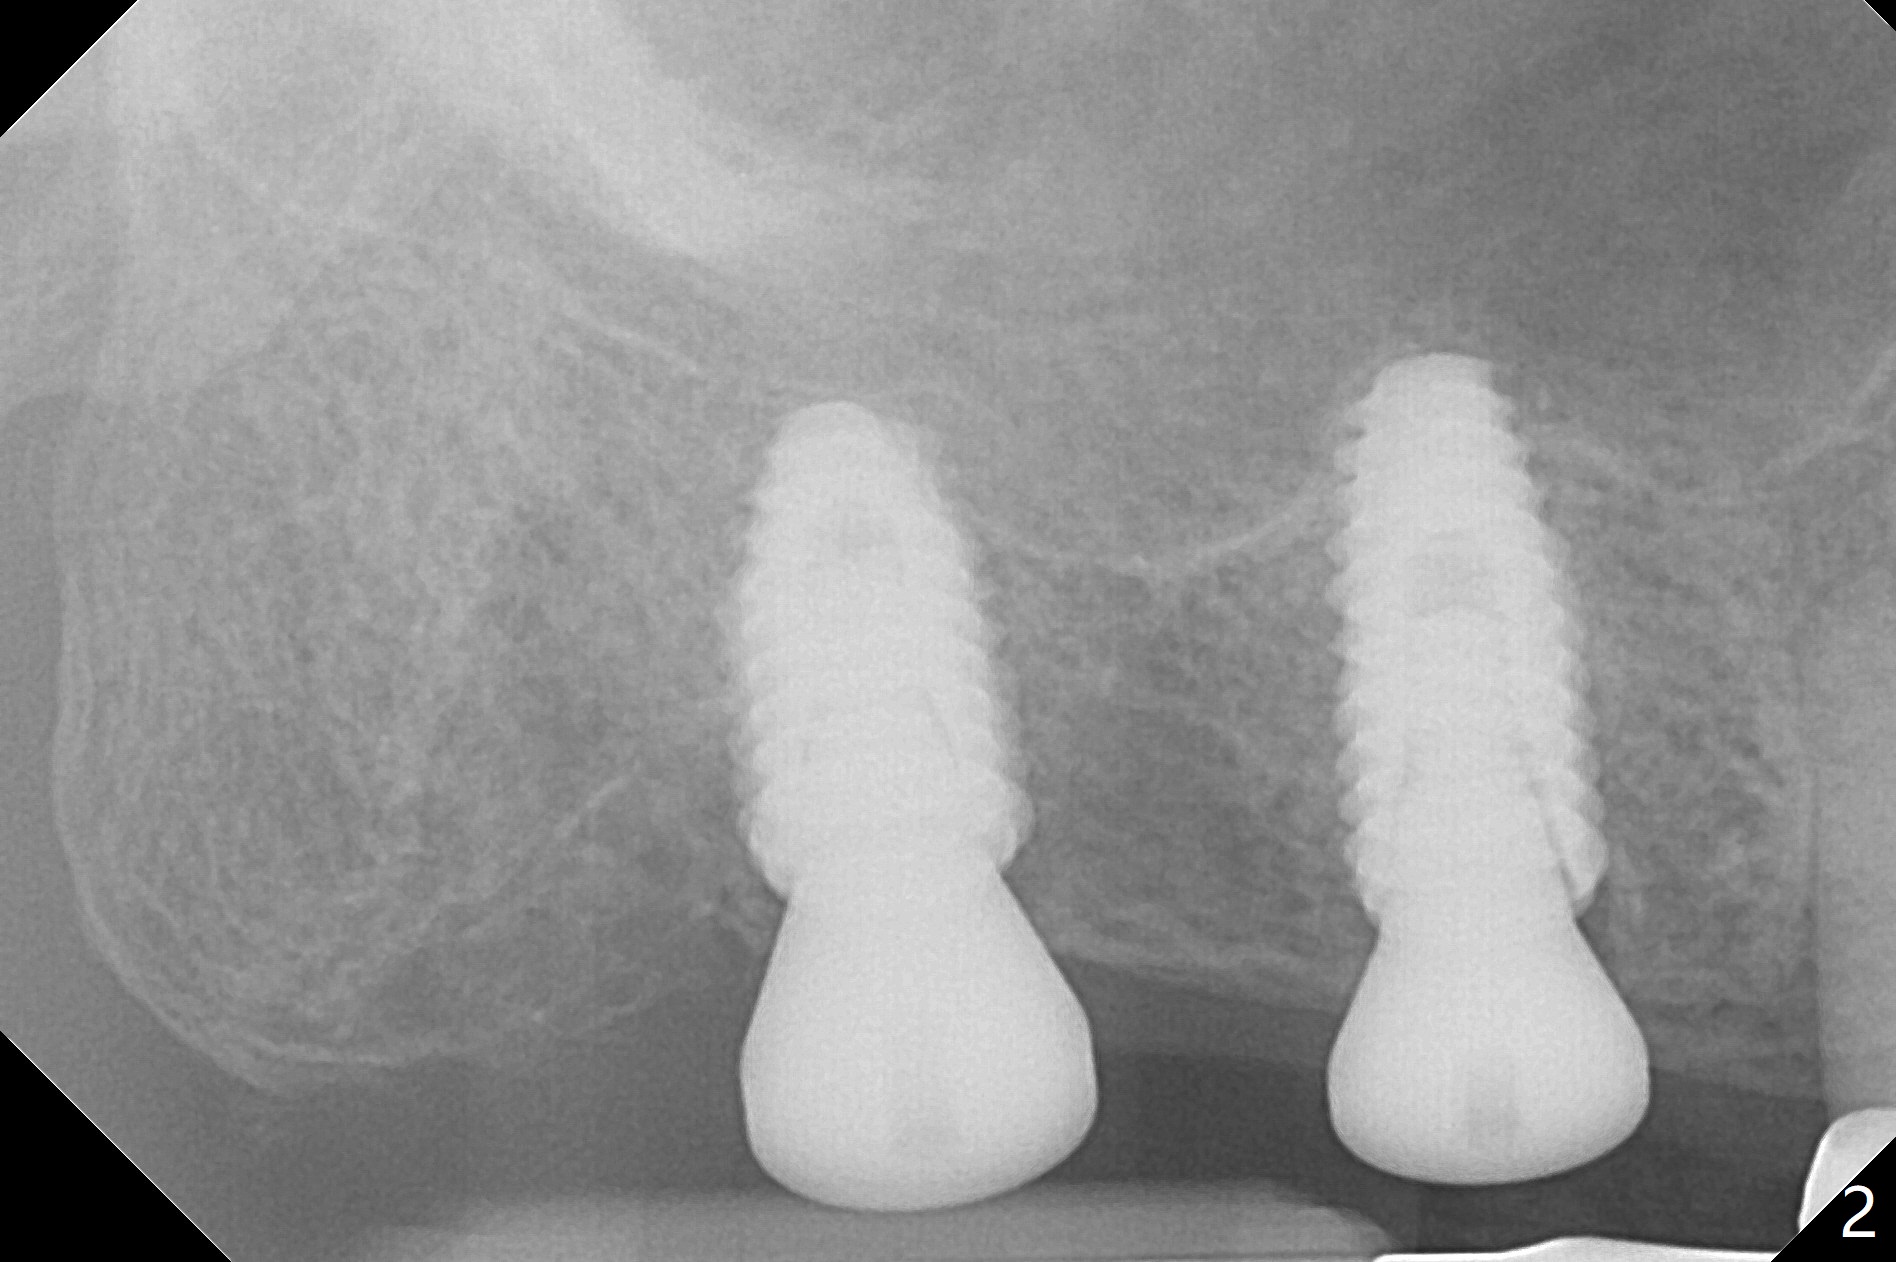

Osteotomy at the sites of #2 and 3 goes on as planned. Sinus lift using DIO 2.8 mm round bur with 6 and 7 mm stoppers (respectively) is carried on without certainty, because it is difficult to feel the stop through the osteotomy. The crest may be uneven or soft. It appears that the soft tissue landmark as a stop may be easier to identify. In fact a 3 mm IBS Magic Expander (an osteotome) was used for sinus lift at #3. The 2 implants are placed with 20 and 30 Ncm (Fig.1,2). Healing abutments are inserted. At 2-week follow-up, the patient reports "pain a few days earlier, took a pill of antibiotic, pain gone. UR metal is sharp". She does not take antibiotic regularly. Exam reveals that there is heavy plaque around #2,3 healing abutments. The buccal edge of #2 abutment is trimmed for comfort. Nearly 1 month postop, #3 healing abutment dislodges with buccal gingival erythema and edema with purulent discharge (Fig.3). Healing screw is placed at #3 with Amoxicillin and Chlorhexidine prescribed. One week later, the implant at #3 turns when the healing screw is retightened (Fig.4). After debridement, Vanilla graft is placed. There is no infection at #2 or 3 four months postop (Fig.5,6); the lingual gingiva is erythematous and edematous at #29 with mobility II (Fig.7 (vertical root fracture)). Uncover is conducted at the site of #3; there is no infection superficial 7.5 months postop (Fig.8). There is a large buccal defect upon incision with dark hemorrhage. In fact the bone density is low crestally (Fig.8 *). Bone graft is placed for the 2nd time. Eleven months later (1.5 years post implant placement), the bone regrows crestal (Fig.9 *). The crown at #3 is loose 1 year 5 months post cementation (Fig.10). After proximal trimming (Fig.11 *), the abutment at #3 is seated completely. After lab repair, crown oral cement, crown/abutment removal for excess cement removal, the crown/abutment cannot be torqued >25 Ncm (Fig.12, 30 Ncm). PA shows incomplete seating (Fig.12 <). Then the crown is sectioned so that the abutment has more freedom to be seated completely with pressure against the gingiva (the patient feels pain, Fig.13). Torque is 30 Ncm. After crown cementation, the abutment will not be removed for cement removal.